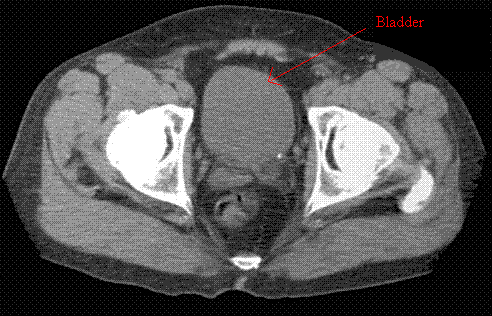

In relationship to the seminal vesicles, the bladder lies where anatomically?

The bladder lies slightly superior and anterior of the seminal vesicles.